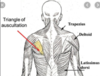

triangle of auscultation

clinical significance of triangle of auscultation

The triangle of auscultation is a region of the posterior thorax devoid of superficial back muscles, which allows for optimal auscultating lung sounds.